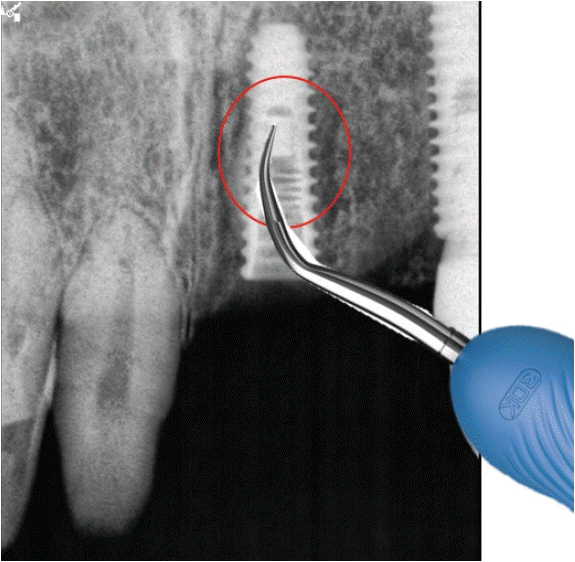

임플란트는 많이 심을수록 확률적으로 실패도 늘어나고 이에 따라 임플란트를 제거해야 하는 경우도 늘어나게 되었다. 2014년 7월 1일 임플란트 제거와 관련된 고시가 새로 발표된 이후로는 단순과 복잡으로 정리되었다. 단순 임플란트제거술은 임플란트 동요도가 있는 경우로 정의되어 구강내 식립 위치에 무관하게 적용되고 있다. 반면에 복잡 임프란트제거술은 동요도가 없는 경우에 임플란트 주위염, 파절 신경손상 등에 적용되는데 trephine bur 또는 별도의 제거 전용 키트를 사용하는 경우에 적용된다. 따라서 버를 사용하지 않더라도 라쳇(rachet)이나 토커렌치(torque rench) 등으로 제거하는 경우에도 적용 가능하다.주의해야 하는 사항은 trephine bur를 사용하고서는 별도의 비용을 추가로 청구하는 것은 허용되지 않는다는 것이다(Fig. 2), trephine bur를 처음 사용하는 경우 주의해야 하는 것은 적용 시에 역회전으로 방향을 먼저 잡은 이후 정방향으로 바꿔서 제거해야 한다는 것이다. 임플란트 보다 사이즈가 큰 것을 사용해야 하는데 시판되는 trephine bur는 내경과 외경이 보통 1mm의 차이를 보인다. 따라서 4mm 직경의 임플란트를 제거하기 위해서는 내경이 4mm 이상 이어야 히고 외경은 5mm 이상이 된다 그러나 현실적으로는 내경이 5mm이상인 것을 적용해야 제거가 쉬우므로 제거 후 결손부가 굉장히 광대하게 발생 된다.임플란트 제거술은 식립된 임플란트가 비보험임플란트인지 여부를 따지지 않고 언제 어디에서 식림된 것인지도 따지지 않는다. 다만 본원에서 식립된 비보험 임플란트가 신경손상이 확인되어 제거할 때에는 비보험임플란트를 보철까지 완료해야 하는 과정 중에 일어난 일이므로 보험적용이 불가하다. 그러나 타원에서 시행된 비보험 임플란트를 제거하는 경우라면 보험 적용이 가능하다,임플란트 제거를 시행한 후 보험임플란트를 바로 식립하는 경우에는 청구가 되지 않고 있다. 두 항목의 동시청구가 인정되지 않는 것이다. 현재로서는 다음 달에 식립 1단계를 청구하늗 것이 해결책이다,- 2. 임플란트 모철물 나사삽입구 재충전